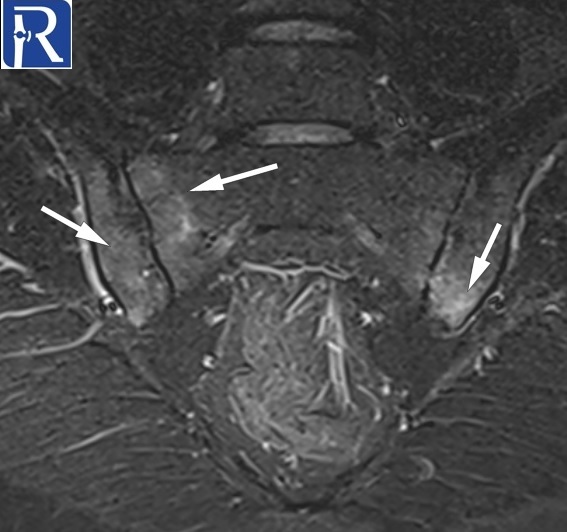

Sacroillitis

Demographic and clinical details: 32-year-old male patient was admitted with low back pain for 5 years.

Image Details: AP pelvis X-ray shows the joint space irregularity and peri-articular sclerosis of bilateral and narrowing of the superior part of the left sacrooiliac joints. There are mltiple erosions in both sides. Findings are consistent with radiographic sacroiliitis according to the New York criteria (Grade II sacroiliitis of right, grade III sacroiliitis of left side). Structural lesions indicated with arrows (fatty metaplasia with white arrows, backfill with the green arrow, erosion with black arrow) are seen on T1 W images. Extensive edema of Active sacroiliitis (Extensive bone marrow edema of osteitis (white arrows) is seen on the STIR image. Findings are consistent with active enthesitis (green arrows) and spondylitis (thin white arrows) are also seen on subsequent coronal STIR images. Active arthritis of left L5-S1 facet joint (blue arrow) and active enthesitis of posterior part of the left iliac bone (green arrow) are seen on the fat-suppressed T2 W image. Radiological findings are consistent with radiographic axial spondyloarthritis (ankylosing spondyloarthritis).